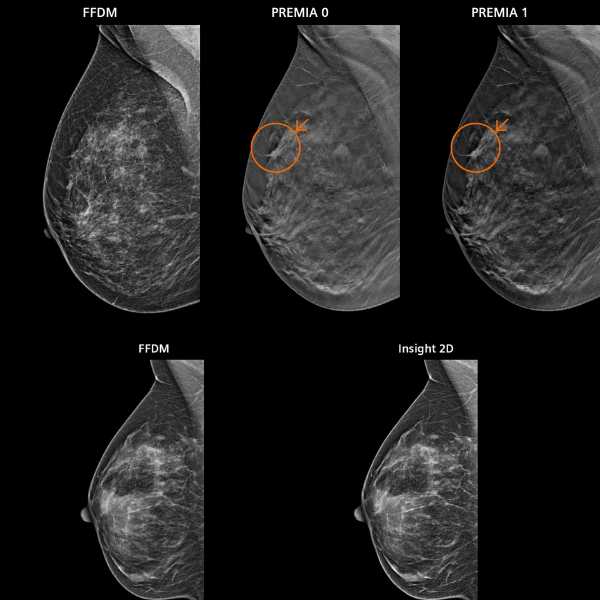

Gracias a la innovadora tecnología PlatinumTomo, el MAMMOMAT B.brilliant ofrece una adquisición avanzada de imágenes por tomosíntesis, mejorando la visualización de lesiones y reduciendo la superposición de tejidos. Su escaneo ultrarrápido, con tomosíntesis de gran angular de 50° en solo 5 segundos, optimiza el flujo de trabajo y mejora la comodidad de la paciente durante el estudio.

El sistema proporciona excelente resolución en plano y mayor definición en profundidad, con opciones de impresión de imagen personalizable según las necesidades clínicas. Su diseño ergonómico e interfaz intuitiva están pensados para maximizar la eficiencia del técnico radiólogo y la seguridad del paciente.